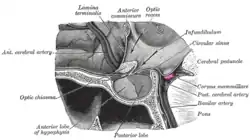

Sagittal section, "Corpus mamillare" highlighted.[1] | |

Coronal section of brain through intermediate mass of third ventricle. (Label "Corpora mamillaria" at bottom.) | |

The mammillary bodies also mamillary bodies, are a pair of small round brainstem nuclei.[2] They are located on the undersurface of the brain that, as part of the diencephalon, form part of the limbic system. They are located at the ends of the anterior arches of the fornix.[3] They consist of two groups of nuclei, the medial mammillary nuclei and the lateral mammillary nuclei.[4]

Neuroanatomists have often categorized the mammillary bodies as part of the posterior part of hypothalamus.[5]

They are connected to other parts of the brain (as shown in the schematic, below left), and act as a relay for impulses coming from the amygdalae and hippocampi, via the mamillothalamic tract to the thalamus.